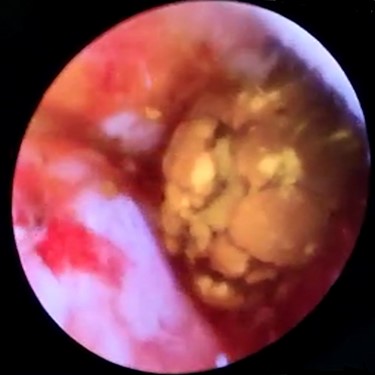

In context of purulent cholangitis, a 10 mm stone was reached (Fig. 4) and extracted with Dormia basket under direct vision (Fig. 5). Furthermore, control choledochoscopy and cholangiography did not show any other stones in the CBD and contrast easily passed into the duodenum (Fig. 6).